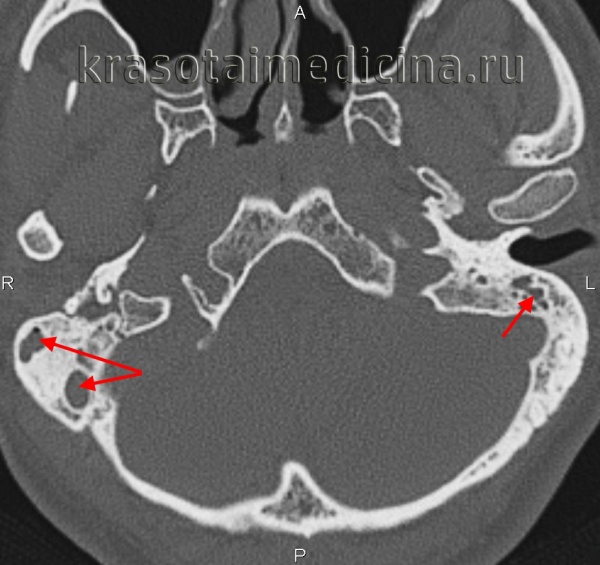

Двусторонняя пневматизация верхушки пирамиды височной кости. Изображение при КТ напоминает аэрированные трабекулярные структуры сосцевидного отростка.